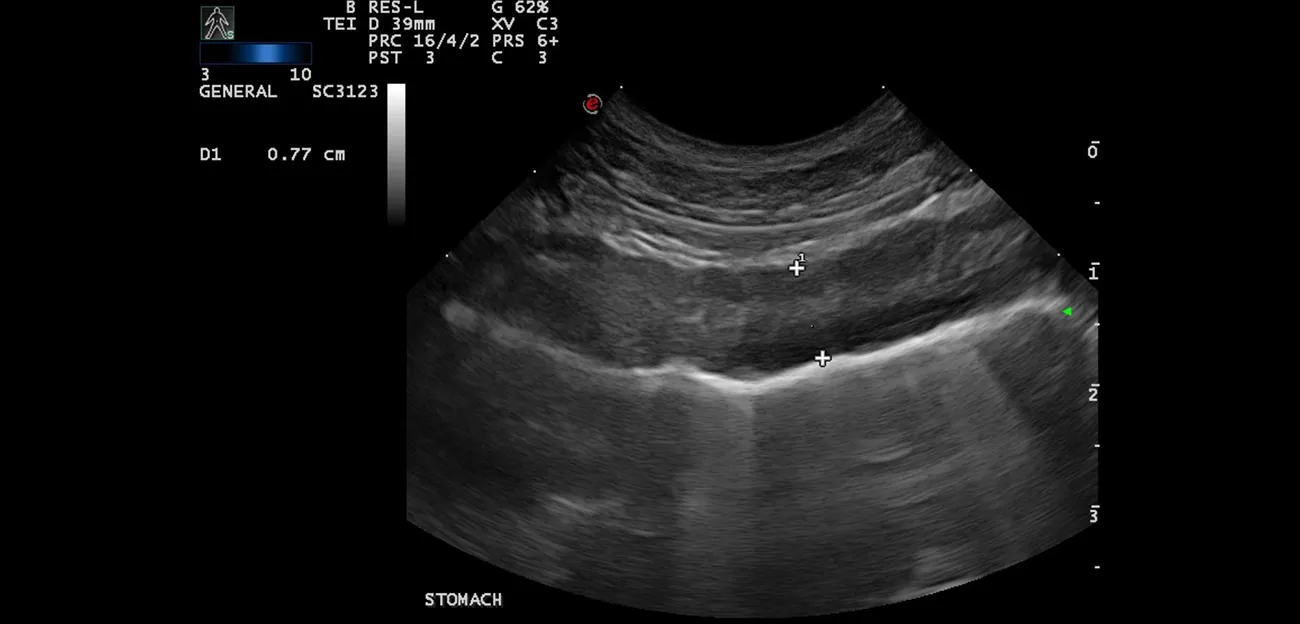

Ultrasound image of the stomach wall of a dog.